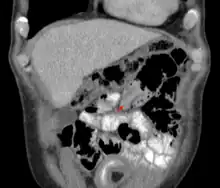

| An intussusception as seen on CT | |

An intussusception is often suspected based on history and physical exam, including observation of Dance's sign. A digital rectal examination is particularly helpful in children, as part of the intussusceptum may be felt by the finger. A definite diagnosis often requires confirmation by diagnostic imaging modalities. Ultrasound is the imaging modality of choice for diagnosis and exclusion of intussusception, due to its high accuracy and lack of radiation. The appearance of target sign (also called "doughnut sign" on a sonograph, usually around 3 cm in diameter, confirms the diagnosis. The image seen on transverse sonography or computed tomography is that of a doughnut shape, created by the hyperechoic central core of bowel and mesentery surrounded by the hypoechoic outer edematous bowel.[11] In longitudinal imaging, intussusception resembles a sandwich.[11] It is also called "pseudokidney" sign because hyperechoic tubular centre is covered by a hypoechoic rim producing a kidney-like appearance.[12]